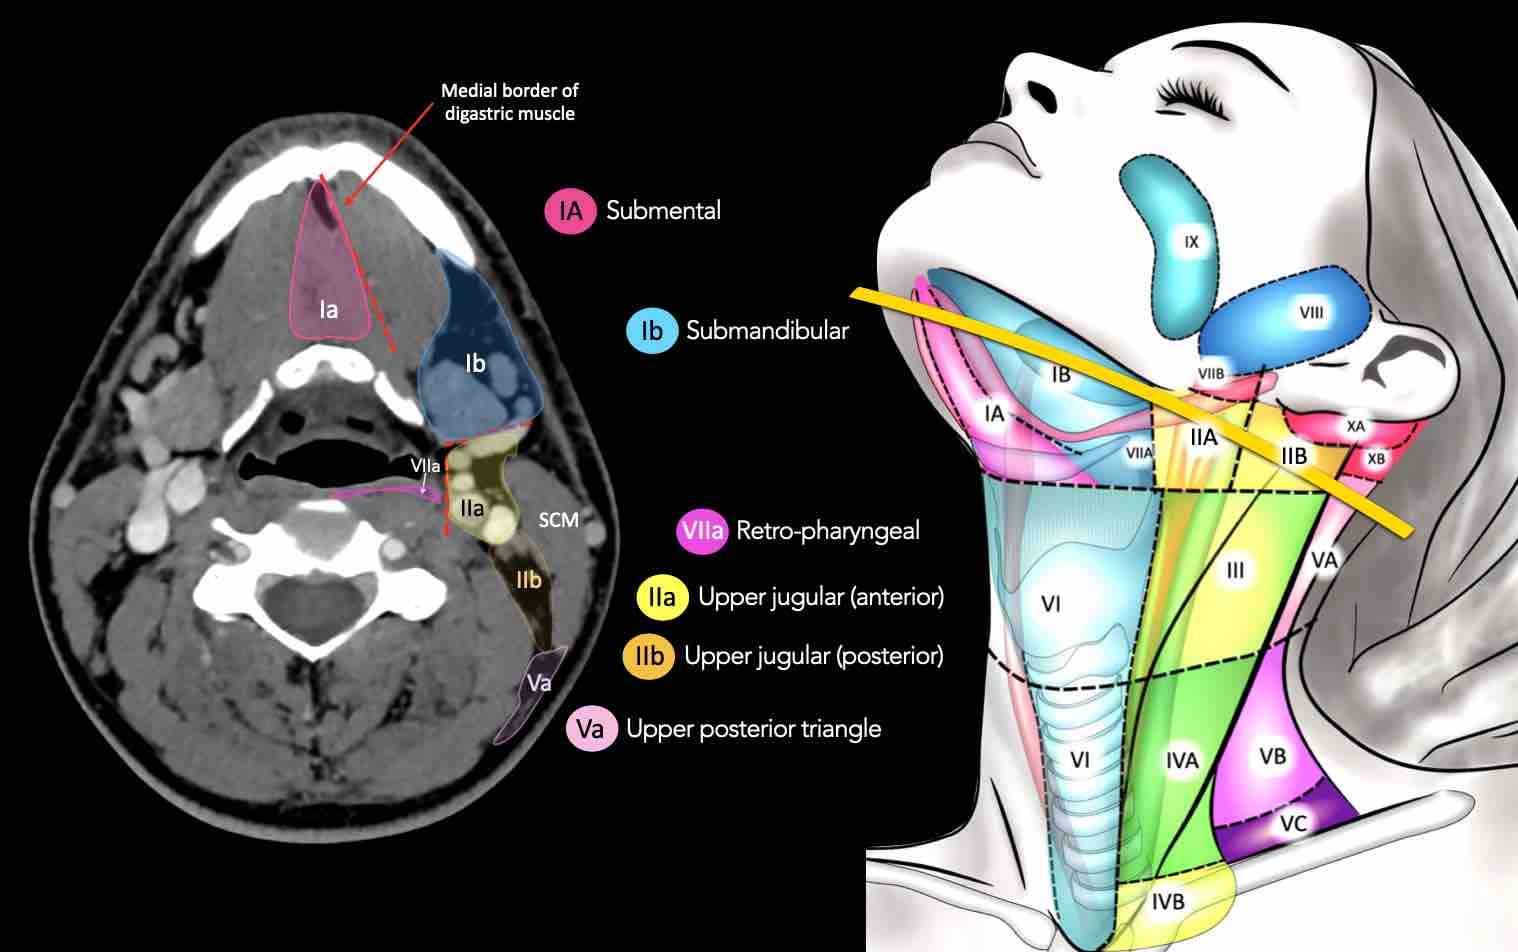

CT Scan Mặt Cắt Ngang (Axial CT)

Các lát cắt CT mặt phẳng ngang tương ứng với hình minh họa tổng quan.

Các lát cắt CT mặt phẳng ngang với hình ảnh chi tiết hơn.

Nhấp vào hình ảnh để phóng to.

I – Dưới cằm và dưới hàm

Các hạch bạch huyết ở tầng I có nguy cơ phát triển di căn từ các ung thư khoang miệng, hốc mũi trước, mô mềm vùng mặt giữa và tuyến dưới hàm.

Tầng Ia

là vùng giữa nằm giữa bụng trước của các cơ nhị thân, chứa các hạch dưới cằm.

Tầng Ib

chứa các hạch dưới hàm nằm trong khoang giữa mặt trong của xương hàm dưới ở phía ngoài và cơ nhị thân ở phía trong, từ khớp mu cằm ở phía trước đến tuyến dưới hàm ở phía sau.

II – Tĩnh mạch cảnh trên

Tầng II có thể được chia thành tầng IIa và tầng IIb bằng cách vẽ một đường tại bờ sau của tĩnh mạch cảnh trong.

Các hạch bạch huyết ở tầng IIa và IIb có nguy cơ chứa di căn từ các ung thư hốc mũi và khoang miệng, vòm hầu, hầu miệng, hạ hầu, thanh quản và các tuyến nước bọt lớn.